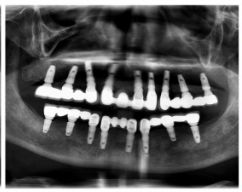

種牙前照片

通過X光片可以看到,醫(yī)生雖然盡量設計連冠種植,但還是用了十七個植體,盡管已經(jīng)是多次調整后的精簡方案,但手術時長依然長達一天。位老先生之前在另一家醫(yī)院咨詢時,醫(yī)生給的方案是種二十二個植體,光是種植費用就令人大呼“害怕”了。